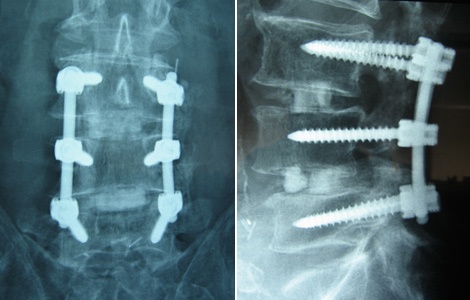

I was recently at a seminar of 2 – 300 chiropractors and a surgeon was speaking. The surgeon asked what percentage of our patients end